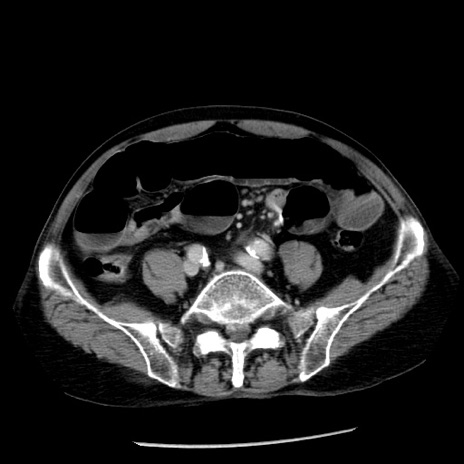

症例26(横断像)

【症例】80歳代男性

【主訴】嘔吐

【現病歴】昨晩2回嘔吐あり、今朝になっても嘔吐あり。来院。

【既往歴】胃潰瘍

【身体所見】意識清明、BT 37.6℃、BP 166/95mmHg、HR 100bpm、SpO2 97%、腹部:平坦・軟、腸蠕動音聴取良好、圧痛なし。

【データ】WBC 21900、CRP 1.46